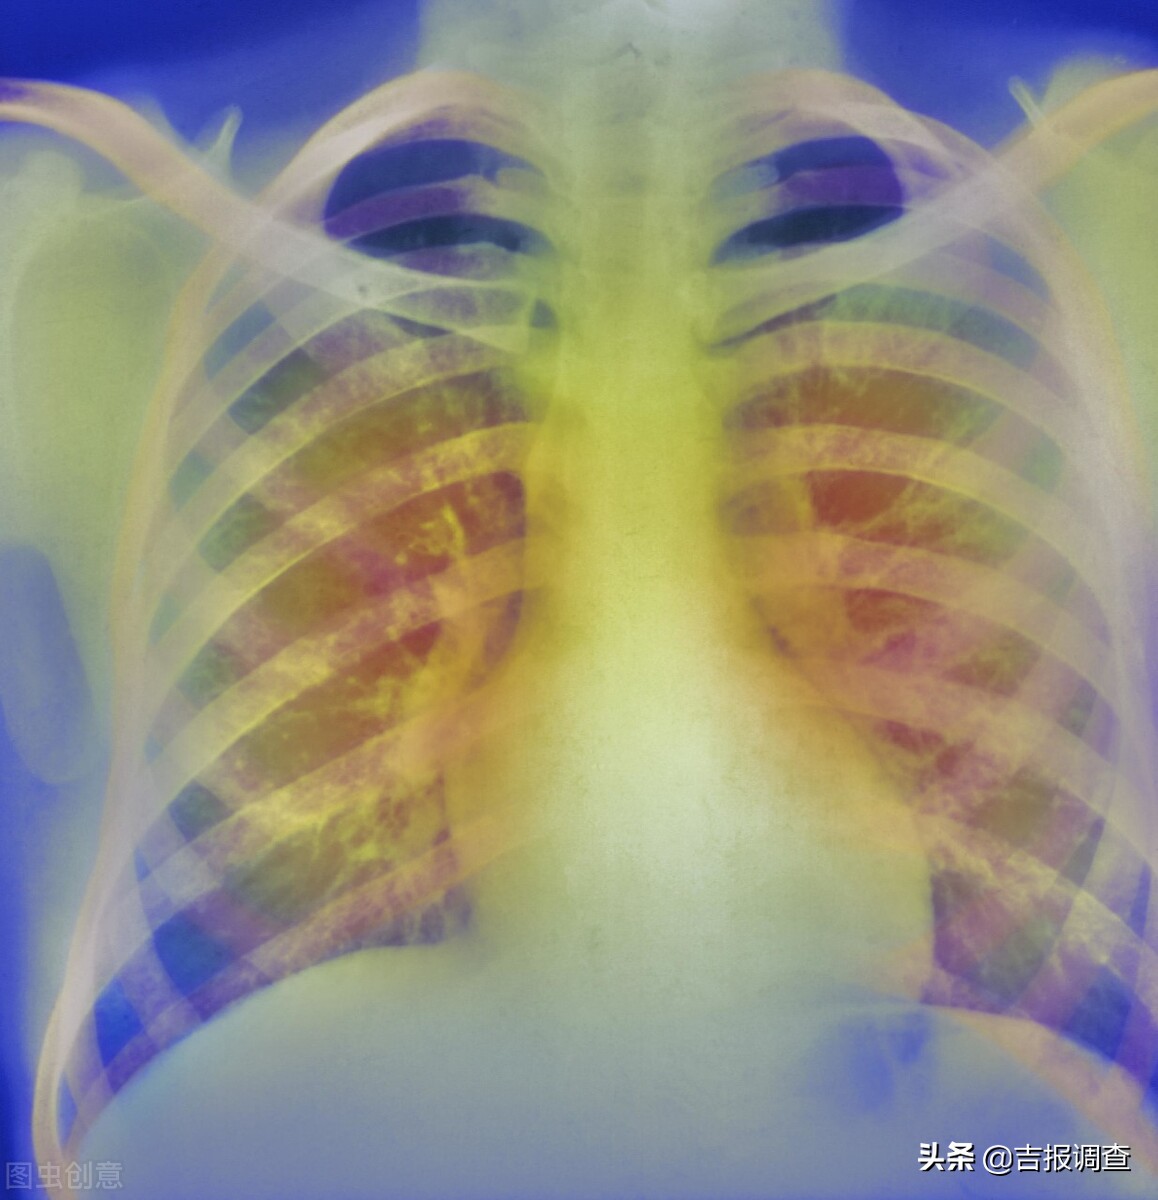

夏天来了,北京弘医堂中医专家给慢性肺病患者提个醒:慢性肺病好发于冬季,到了夏季,咳、喘、呼吸受限、活动困难等状况均有所缓解,很多患者会因此放松对疾病的关注和治疗。其实夏季是肺部慢性疾病康复的最佳季节,对于肺气肿、慢支炎、慢性阻塞性肺炎、间质性肺病等肺病患者来说,尤为重要。

慢性肺病大多病程较长,病情复杂。慢性支气管炎、慢阻肺、支气管哮喘、肺源性心脏病等疾病,多是由肺系急性病变未及时适当治疗,或原本体质虚弱,反复感染外邪迁延发展而致。夏季气温升高,人体血液循环较好,慢支炎、肺气肿、支气管哮喘等病症表现往往不明显,致使许多患者产生疾病好转的错觉,从而放松警惕,如不及时治疗,常常会失去治疗的最好机会,此时如果忽视对疾病的巩固治疗,对于各类慢性肺病患者来说,是极其不利的。